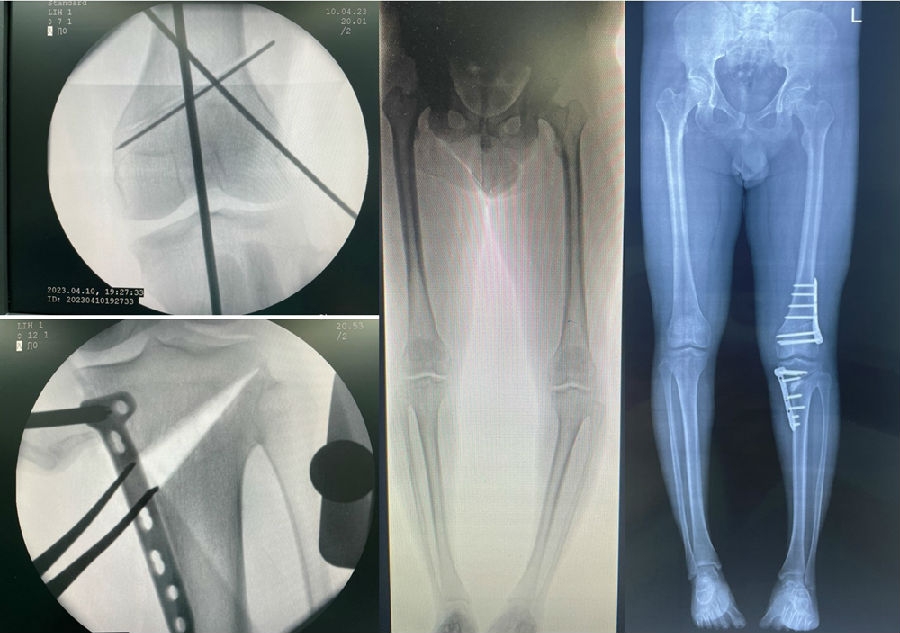

经典病例

总结

双截骨术:恢复下肢力线,关节线平行地面;

适应证:股骨侧畸形+胫骨侧畸形;

术前设计:以关节线为参考,设定目标力线;

手术策略:第一侧放平关节线,第二侧达到目标力线。